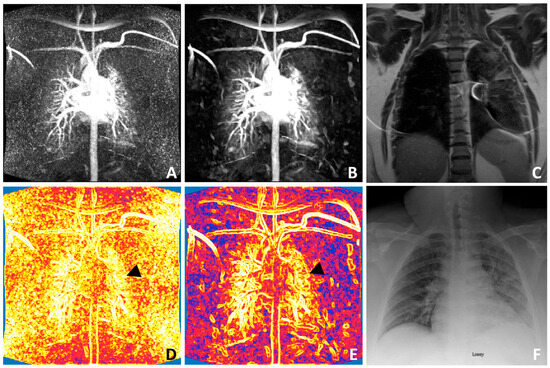

3.2. Patient Example: Pulmonary Embolism Case Study

3.3. Comparison with Reference Clinical Imaging